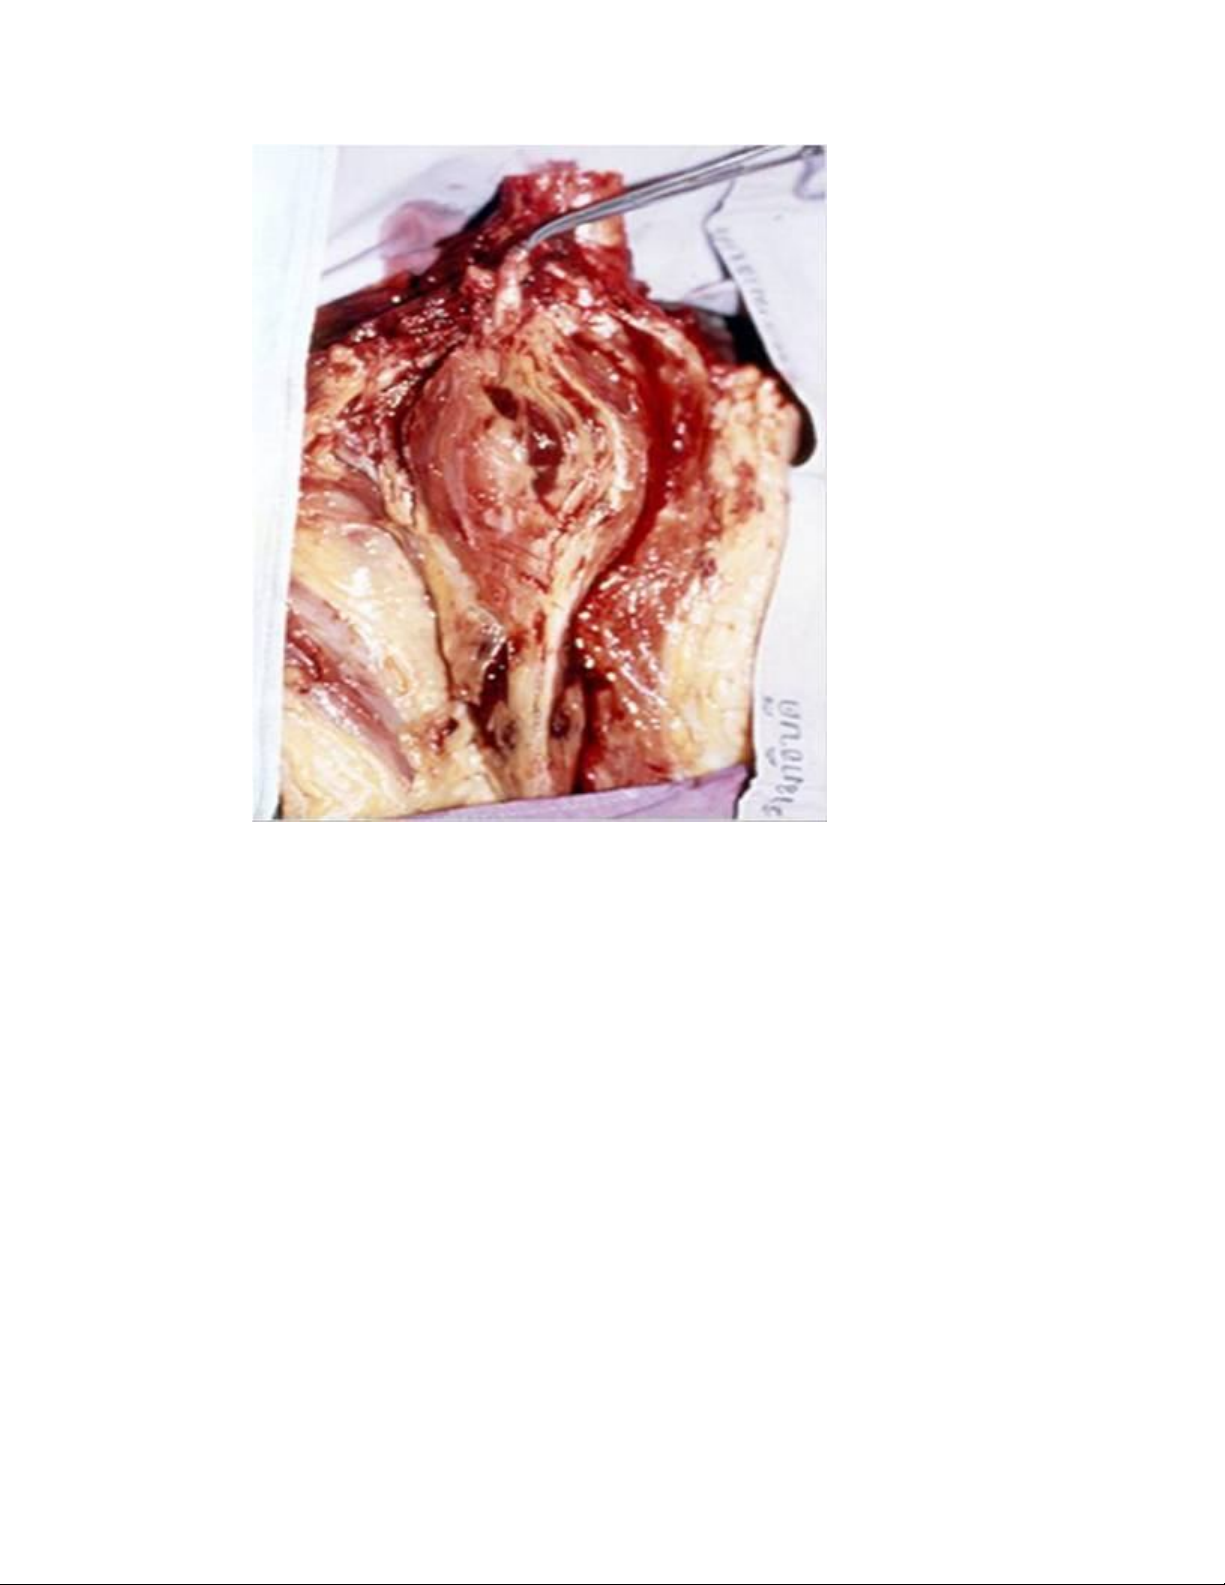

Túi phình động mạch được cắt bỏ